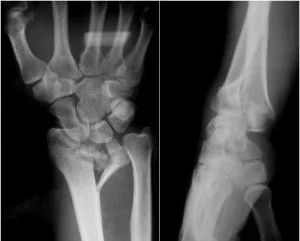

1.- Fractura de Pouteau-Colles: según este, es la lesión más común de la extremidad distal del radio. Es la fractura de la epífisis distal del radio, con desplazamiento hacia dorsal y radial. Es la más común de todas las fracturas, se observa fundamentalmente en la mujer anciana o de mediana edad, siendo la osteoporosis un factor contribuyente.

El contorno alterado de la muñeca en una fractura de Colles gravemente desplazada es evidente y se designa con “deformidad en dorso de tenedor”.